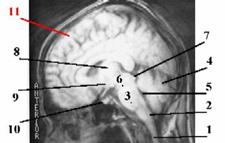

Рис. 15.1.

Головной мозг человека

МРТ

|

| I. Продолговатый мозг (2) | Это непосредственное продолжение спинного мозга (1) в ствол головного мозга. |

| II. Собственно задний мозг | Включает две части: - варолиев мост (3), расположенный вентрально, у основания мозга, и - мозжечок (4), расположенный дорсально. | |

| Общая полость | Остатком полости заднего мозгового пузыря (из которого произошли отделы I и II) является IV желудочек (5) мозга, находящийся на уровне продолговатого мозга и мозжечка. | |

| III. Средний мозг | а) Тоже содержит две части: - ножки мозга (6) (не путать с ножками мозжечка!) и - лежащую над ними пластинку четверохолмия (7) б) Остаток полости среднего мозгового пузыря – узкий канал, т.н. сильвиев водопровод. | |

| IV. Промежуточный мозг | а) Включает - зрительные бугры (8) (лат. в ед. ч. – thalamus) – большие парные скопления серого вещества, в которых происходит переключение почти всех афферентных путей, идущих в высшие отделы мозга, и - высшие центры регуляции эндокринных функций – эпифиз, гипоталамус (9) и гипофиз (10). б) Между зрительными буграми – щелевидный III желудочек мозга. | |

| V. Конечный мозг | а) Представлен большими полушариями (11), в которых выделяют обонятельный мозг (это эволюционно наиболее древняя часть конечного мозга), серое вещество – в виде подкорковых ядер и коры полушарий, и белое вещество – многочисленные проводящие пути. б) Остатками полости переднего мозгового пузыря являются (наряду с III желудочком) два боковых желудочка в глубине полушарий |